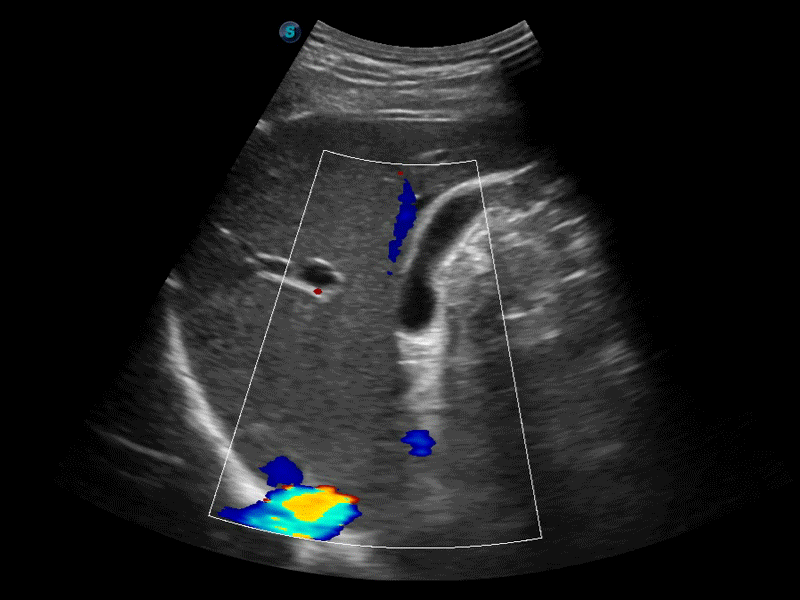

自动识别前后壁内膜厚度,为心血管疾病早期评估提供快速准确依据。